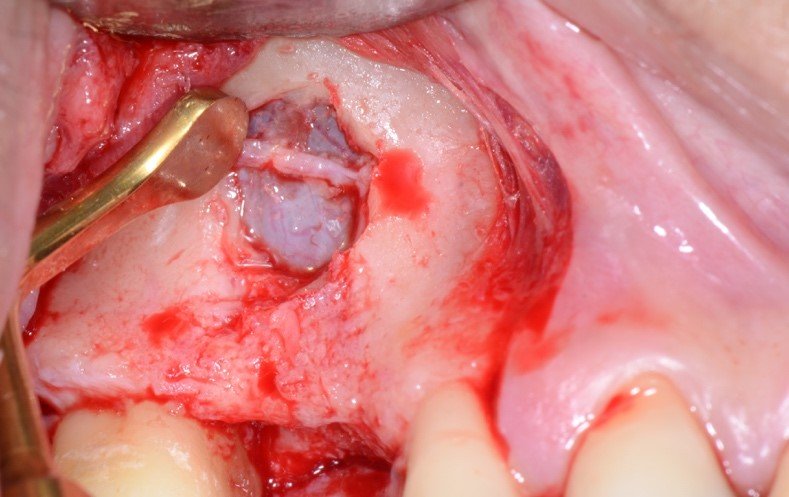

As figuras 16 e 17 mostram o transoperatório de um caso de hemorragia após dano a AAPS durante procedimento de osteotomia para rotação superior da janela óssea. A hemorragia durante a cirurgia trouxe dificuldades na visualização da membrana e a mobilização da janela para o interior da cavidade para formar o teto sobre a membrana sinusal. Somente após o preenchimento total com enxerto ósseo bovino particulado e cobertura com membrana hemostática de colágeno, houve diminuição do fluxo sanguíneo local. Mesmo com a manobra transoperatória, ocorreu a formação de extenso blefarohematoma periorbital e hematoma cérvico-facial. Segundo relato da paciente, o edema palpebral e na região parotídeo-masseterina provocaram dificuldade na abertura palpebral e bucal. As figuras 18 e 19 demonstram os hematomas já em regressão no 110 dia de pós-operatório (PO), já em uso de compressas mornas desde o 70 dia de PO, associado a moderada massagem local para drenagem hemo-linfática nos tecidos com pomada fibrinolítica.